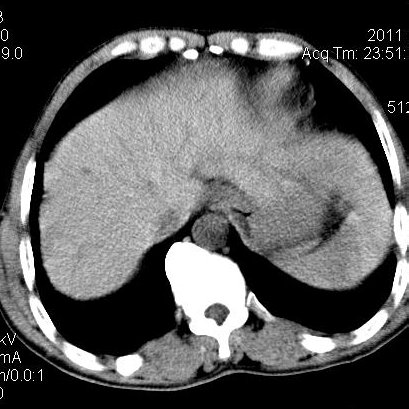

肝左叶发育异常

男性,55岁,骑摩托车摔倒后入院,自述右上腹疼痛

[backcolor=#FF0000]第一次诊断的时候也是这么肯定,可是床旁超声检查并没有发现明显异常,而且患者的一般症状都良好。还好临床只是保守治疗,没有立即手术,第二次复查的时候没有一点变化,又做了MRI检查,没有血肿,

这是一例肝左叶发育异常的,很个性吧~[/backcolor]